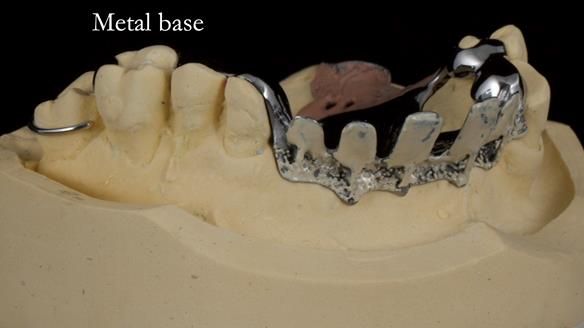

Keith’s case was one of the most challenging and rewarding cases I’ve treated this year. This 64 year old man presented with ill-fitting acrylic partial dentures that lacked stability, retention, and aesthetics. They constantly broke. He had lost the upper front teeth in a road traffic accident in his early 20s. The unopposed teeth had erupted, taking up space. After careful planning, we made a durable, metal-based upper partial denture/splint to address his dental concerns. He loved the outcome.

1. Denture design: A custom cobalt-chromium framework was Scandinavian-designed to maximise stability, protect the remaining teeth, and allow for future additions if needed.

Keith’s denture incorporated a Duracetal shell clasp on upper right first premolar (Myerson), which are designed to be virtually visible, providing a more aesthetic solution while enhancing patient comfort. The Scandinavian-inspired approach, based in modern removable prosthodontic techniques, ensured the denture was not only durable but also visually pleasing. Additionally, the design was carefully planned to allow for future modifications, ensuring that if Keith loses additional teeth, the denture can be adapted rather than replaced entirely.